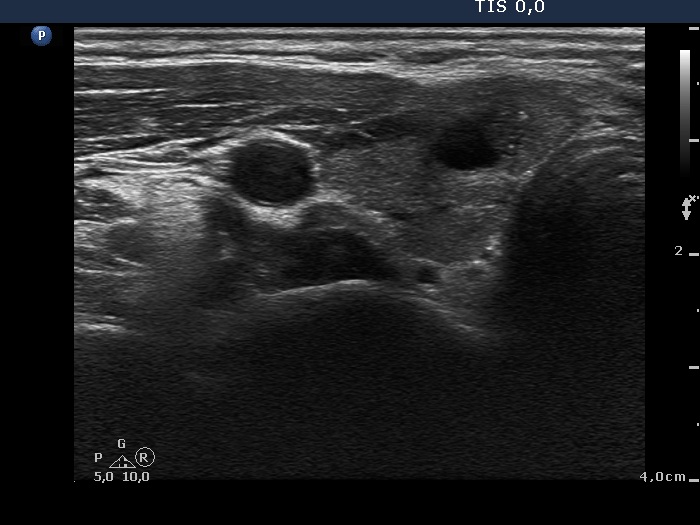

Examination 5 months later (3rd row of images):

Laboratory tests: minimal degree of hypothyroidism (TSH 4.08 mIU/L, FT4 11.5 pM/L), CRP 0.7 mg/L.

Ultrasonography: the thyroid decreased in size as did the extent of hypoechogenic areas. The vascularization was unchanged. There was a cystic lesion presenting microcalcification in the solid part in the lower part of the right lobe. We reviewed the video of the first examination and noticed that the lesion was already present but much smaller. The difference in size was explained by the lack at cystic component at first investigation.

Cytology from the cystic lesion in the right lobe resulted in papillary carcinoma.

Total thyroidectomy was performed. Histopathology discloses a papillary carcinoma. It was solitary with a 4 mm maximal diameter. The left lobe displayed no abnormality.